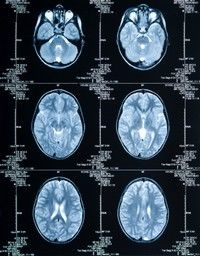

Rezonanta magnetica de 3Tesla: cea mai performanta metoda de diagnostic

Aparatul de rezonanta magnetica de 3Tesla permite obtinerea de imagini a intregului corp cu un timp de expunere redus si o putere mare de rezolutie.

Aparatul de rezonanta magnetica de 3Tesla permite obtinerea de imagini a intregului corp cu un timp de expunere redus si o putere mare de rezolutie.Investigatia prin rezonanta magnetica (iRM) la o intensitate de 3 Tesla este cea mai performanta metoda de diagnostic prin imagine. Investigatia poate diagnostica leziuni cu dimensiuni incepand de la 2 mm. Cu aparatul iRM 3T se pot identifica boli in stadiu incipient, care nu pot fi depistate cu alte aparate de diagnostic imagistic in regiuni ale creierului, maduvei spinarii, cartilagiului articular.

Dintr-un numar de 150 de examinari ale sistemului nervos (creier si maduva spinarii) efectuate in ultimele 2 luni cu aparatul iRM 3T, aproximativ 15% au evidentiat leziuni nevizualizate la examene iRM anterioare, iar in 5% dintre cazuri s-au infirmat leziuni diagnosticate anterior prin iRM.